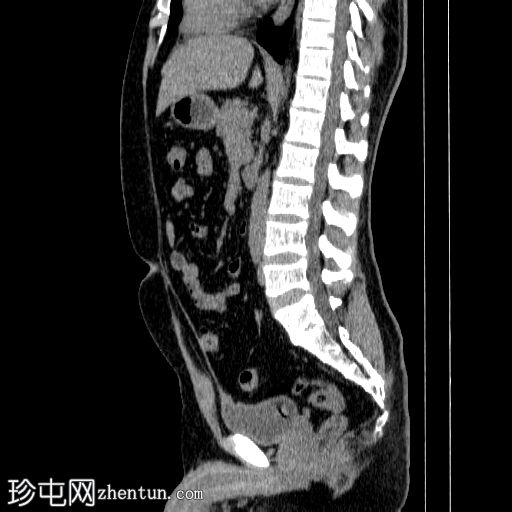

右侧输尿管支架置入。随访CT扫描。

矢状位

平扫

右侧输尿管双J管置入良好,自右肾盂延伸至膀胱。

未见肾积水或肾周积液。

未见输尿管周围脂肪条索状改变。

输尿管支架常用于缓解各种原因引起的尿路梗阻。置入可采用顺行或逆行途径。